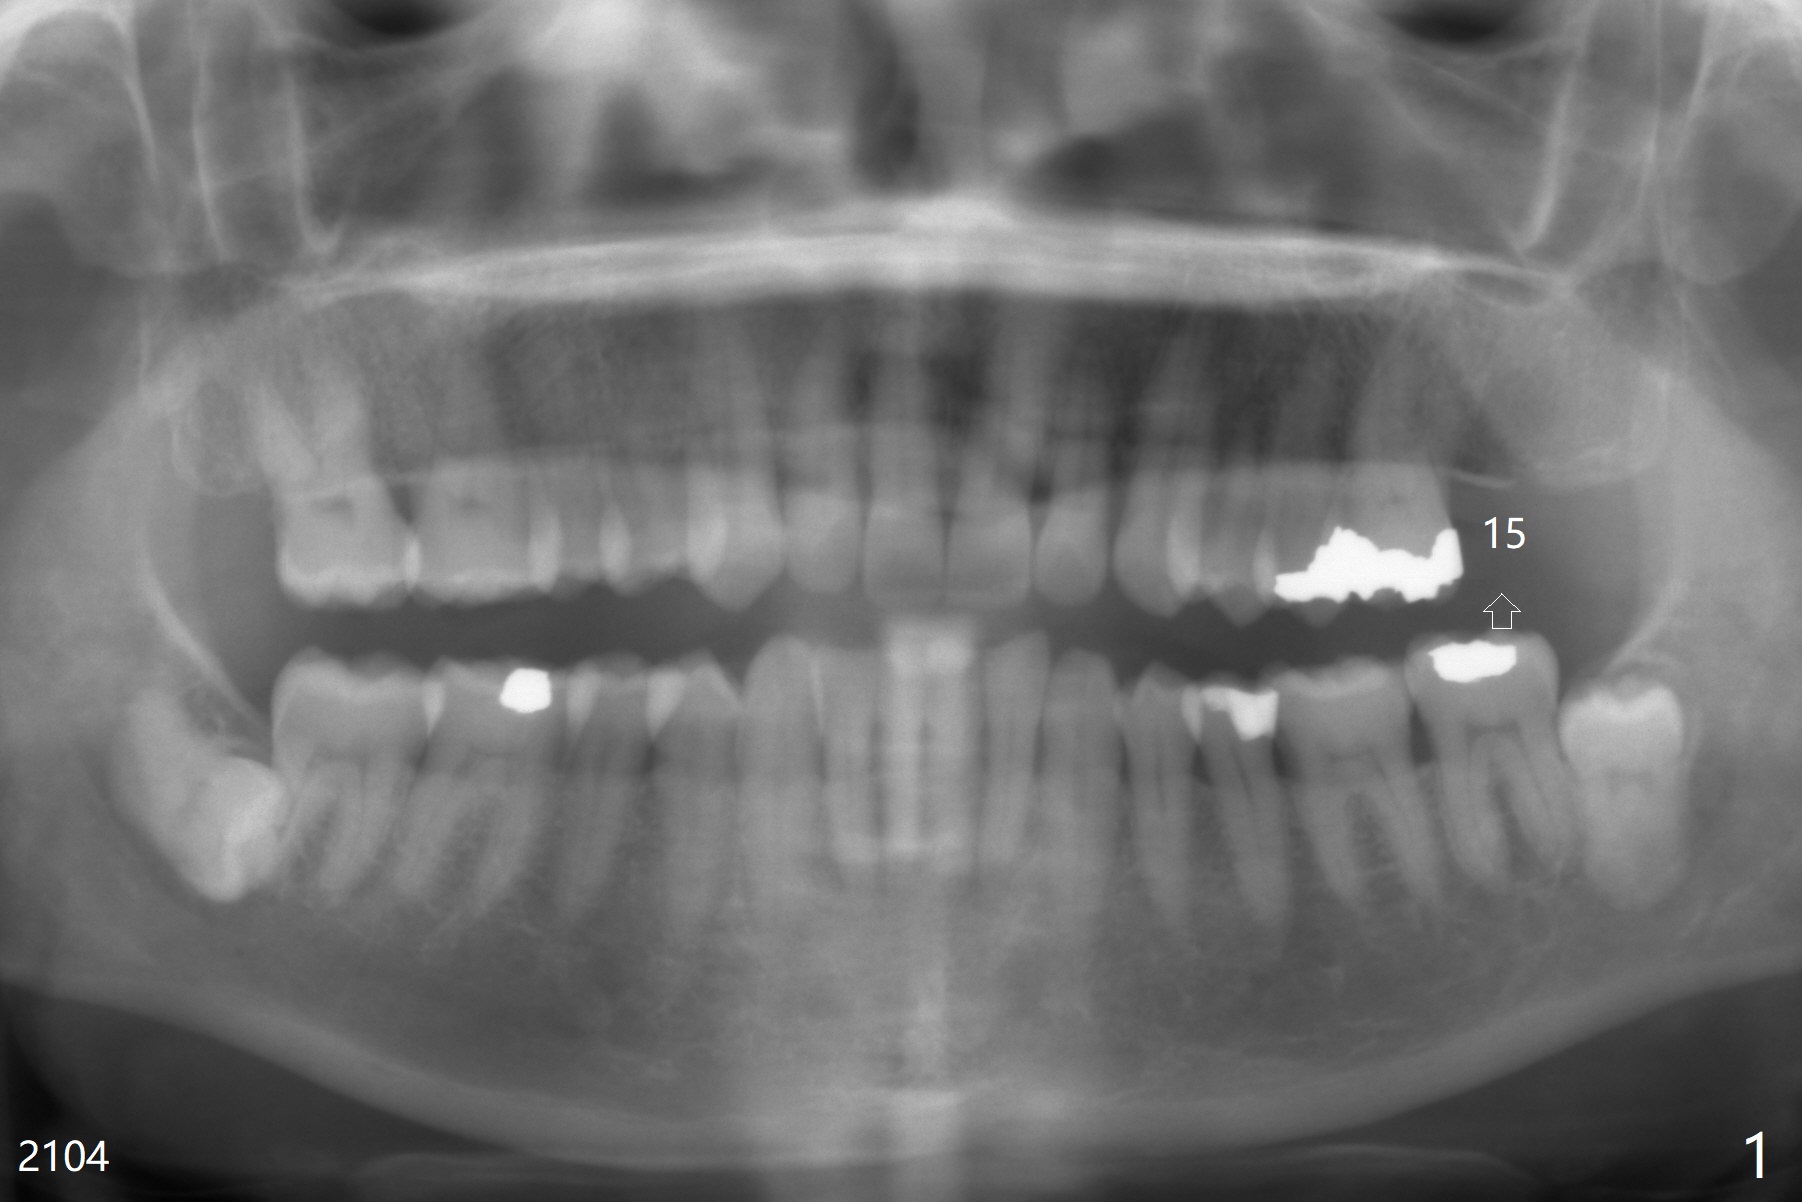

A 65-year-old woman has had signs & symptoms of crack tooth at #3 for the last 4 years (Fig.1-3). Finally the tooth is tender for mastication. Since the socket has infection and the bone is long (Fig.4 red line), an implant will be placed shy of the sinus floor (yellow dashed line). The bone loss (Fig.2,3 ^) may be associated with bruxism, which is detrimental to implant osteointegration. The immediate provisional should have enough occlusal clearance.